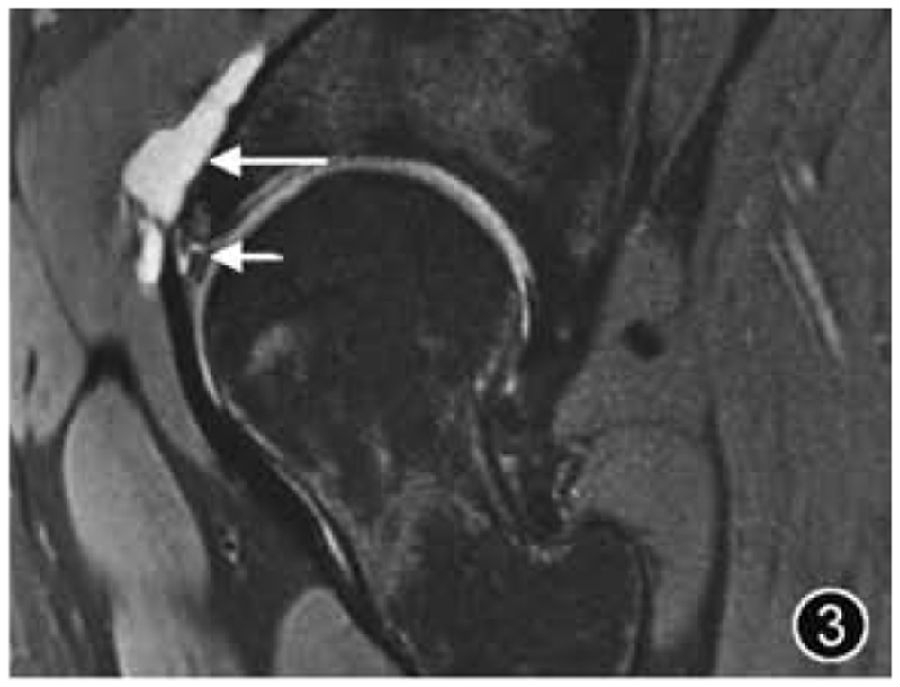

2.髋臼盂唇损伤:髋臼盂唇损伤可能由外伤导致,也可能因关节活动及过度运动而发生退变、磨损和撕裂,DDH、FAI及其他髋关节形态异常易导致盂唇损伤。大多数髋臼盂唇撕裂发生在髋关节的前部或前上区,孤立的盂唇后部撕裂不常见。髋臼盂唇撕裂的位置应使用Blankenbaker 钟面来描述,或者使用传统的解剖描述,如前、前上等。盂唇撕裂可分为部分撕裂和骨盂唇交界处撕裂,两种类型可同时发生。如果盂唇内见局限性高信号,则诊断为盂唇损伤,应报告盂唇形态改变(变薄、增生)、盂唇损伤的性质(退变、磨损)及程度(轻度、中度或重度)。如果观察到自盂唇关节侧穿过盂唇基底部或进入盂唇实质内的线样高信号,则认为存在撕裂(图3),应提及撕裂的位置、分型、长度及是否存在盂唇分离。如果伴有盂唇内或盂唇旁囊肿,应描述大小和位置。

图3 髋臼盂唇撕裂MRI图像。冠状面T2WI示髋臼外上盂唇撕裂(短↑)伴盂旁囊肿形成(长↑)